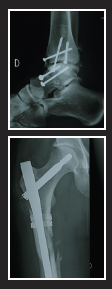

My hands visibly shaking, my toes dug tight into the ridge, I reached for my phone. Jane’s mobile was in her backpack. Four rings later one of the boys answered it. She was alive and conscious. After an agonizing 20-minute wait, Jane was winched into the rescue helicopter and rushed to the intensive care unit at Martigny hospital where the extent of her injuries were reeled off one by one. She’d shattered her right femur and right ankle, and broken her left arm and left ankle. Her helmet and back protector had saved her life.

Jane’s memory of the accident is thankfully pretty vague, but she’ll never forget the long road to recovery. ‘I had a seven-hour operation where my femur and ankle were pieced, then screwed or clipped back in place. The elbow was fixed a week later with two screws. Three weeks after the crash I flew home and started hydrotherapy, at first needing to be hoisted in. After three months I could put my right foot down and then I learnt to walk again in the pool. After six months I was walking everywhere, swimming and cycling. The femur took 18 months to heal and the ankle is still being monitored.